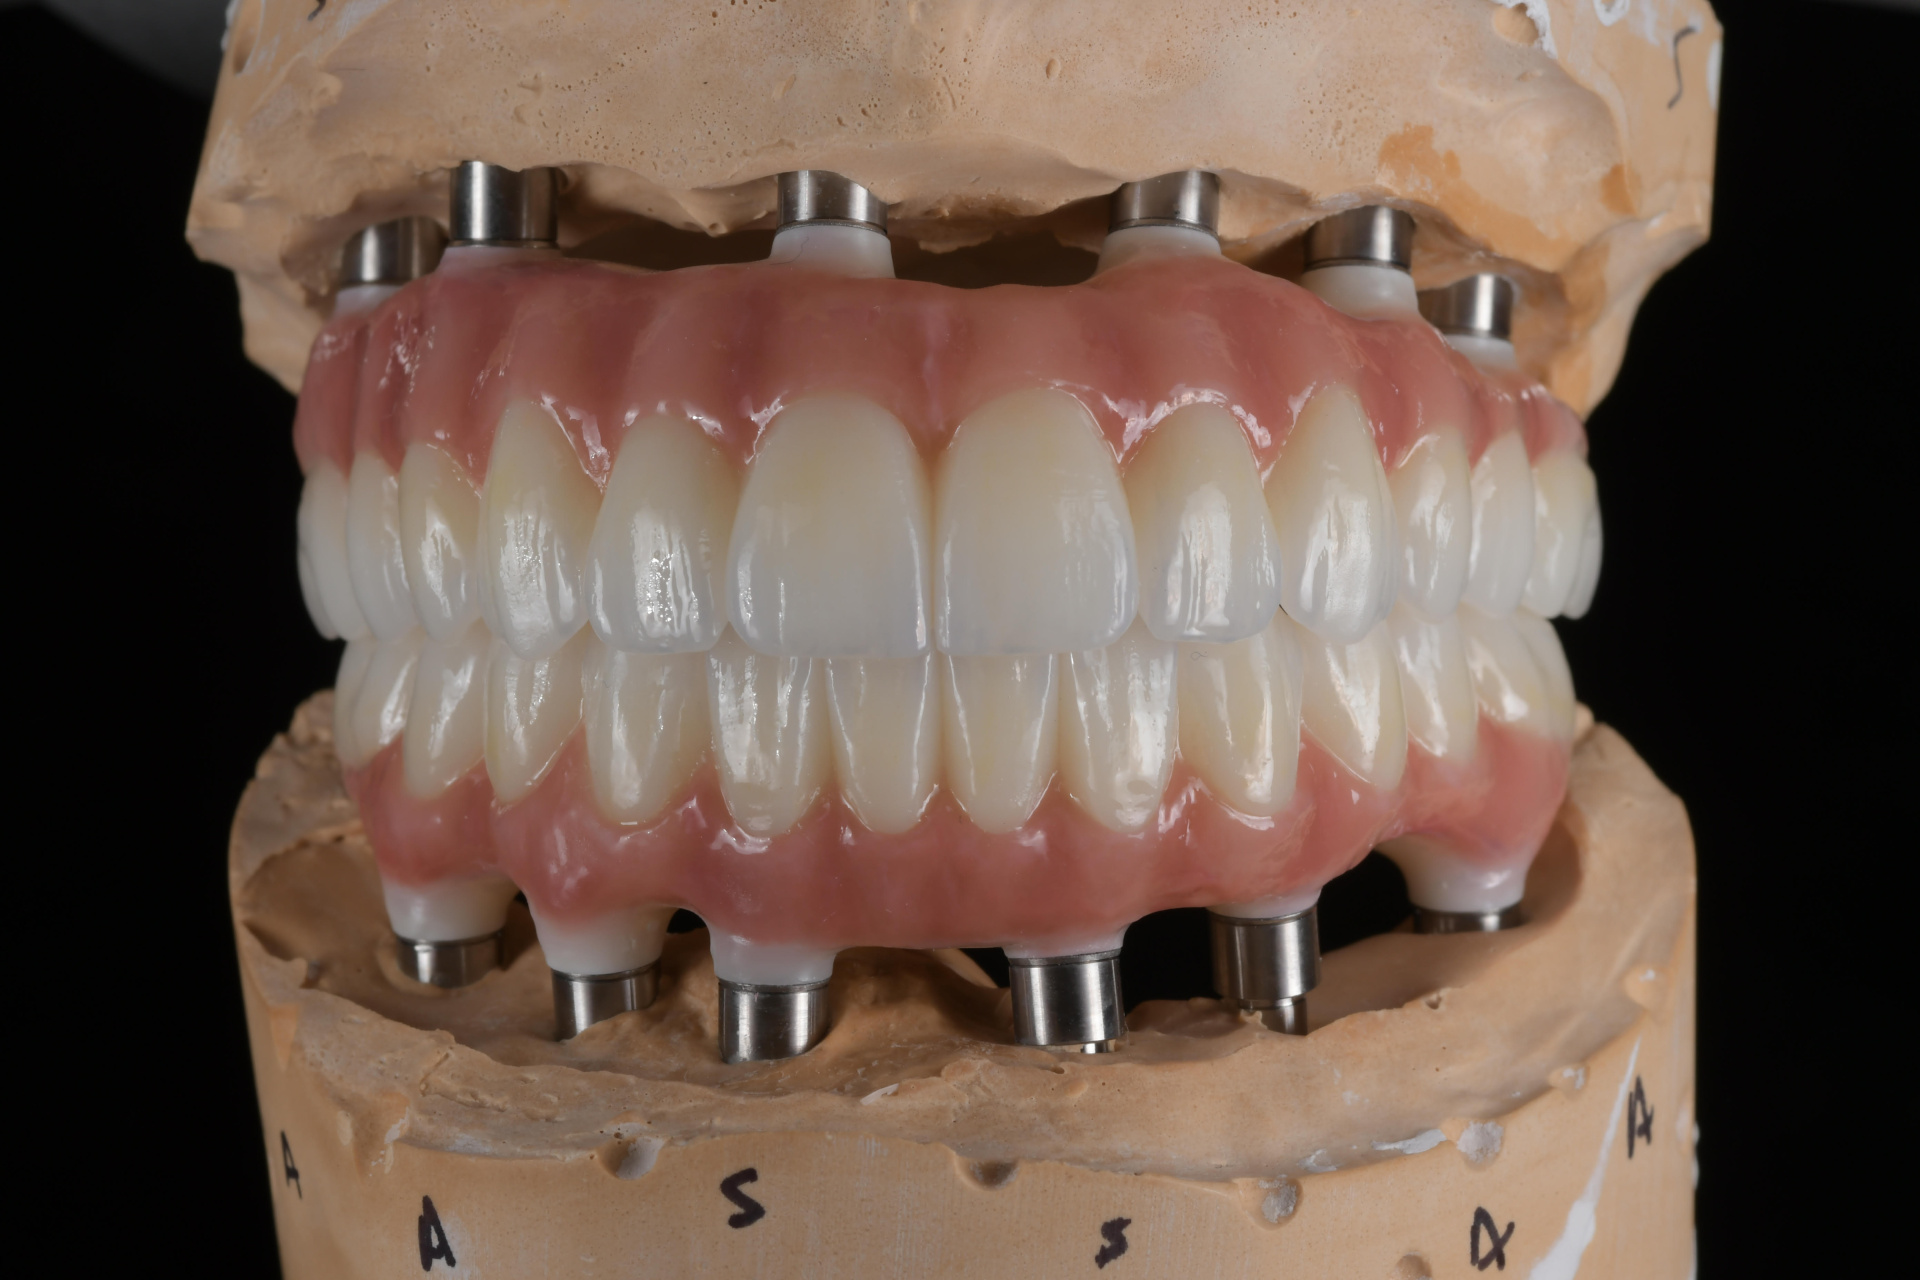

All on 6 for both arches Implants (#3,4,6,11,13,14,18,21,22,27,28,31)